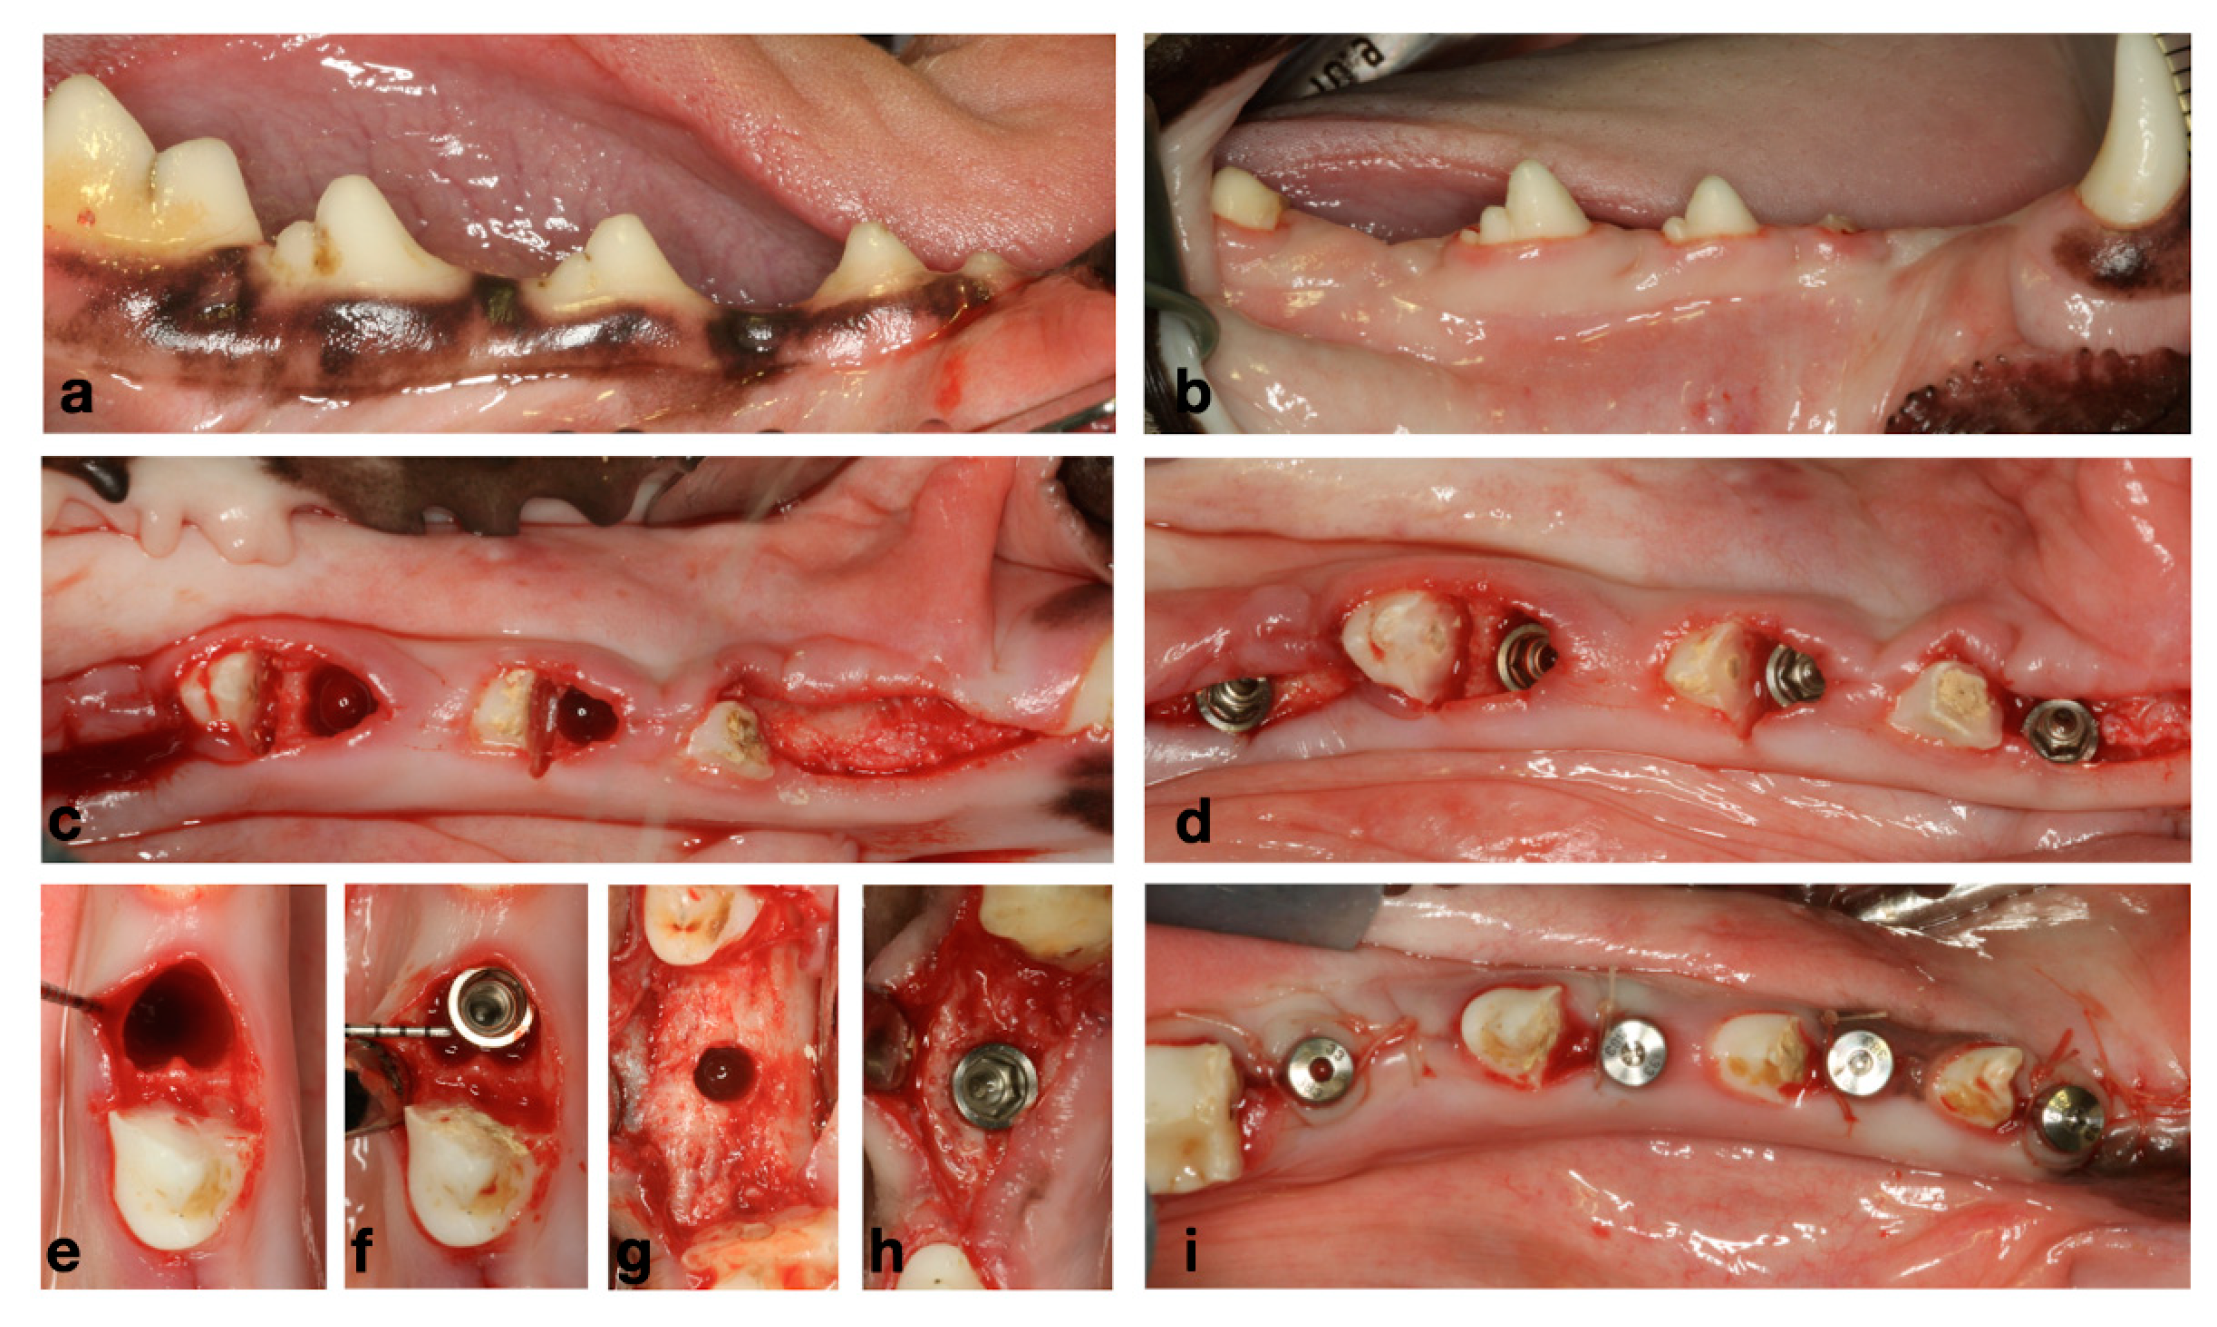

2.2. Experimental Design and Experiments

3.1. Preclinical Observations